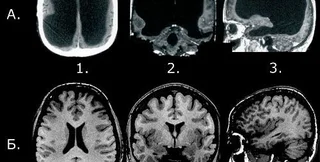

Платные анализы на сканирование мозга при помощи томографии становятся все более популярными среди здоровых людей, которые хотят развеять свои опасения по поводу риска диагноза рака мозга или инсульта.

Медики из университета Эдинбурга (Великобритания) рассмотрели почти 20 тысяч случаев сканирования мозга, проведенных по различным причинам. Среди людей, которым делали мозговую томографию, никто не имел никаких симптомов основных заболеваний мозга.

Неврологи зафиксировали, что даже при обнаружении случайных аномалий работы мозга в 3% случаев (таких как ослабленные кровеносные сосуды или доброкачественная опухоль) не существовало четких медицинских доказательств проведения лечения для таких пациентов.

По мнению ученых, такое отсутствие явных доказательств и показаний для конкретного лечения может ввести пациентов в заблуждение и даже привести к ненужным операциям. Основная трудность подобных медицинских осмотров заключается в неопределенности дальнейших действий для пациента с выявленной дисфункцией мозга.

Исследователи считают, что во избежание неправильных заключений люди должны проходить сканирование головного мозга только при наличии конкретных медицинских рекомендаций или уже установленного диагноза.